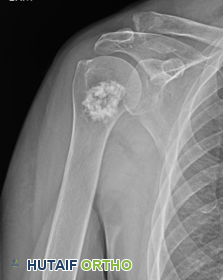

يجب التمييز بين ورم الغضروف الخبيث والورم الغضروفي الداخلي (Enchondroma)، وهو ورم عظمي غضروفي حميد (غير سرطاني) وأكثر شيوعاً. يوجد الورم الغضروفي الداخلي عادةً بالقرب من نهاية العظم القريبة من المفصل (الفيزيولوجيا). الأورام الغضروفية غير السرطانية عادةً ما تكون بدون أعراض ويتم تشخيصها وعلاجها بشكل مختلف عن أورام الغضروف الخبيثة.

بالمقارنة، غالباً ما توجد الأورام الغضروفية الحميدة (مثل الورم الغضروفي الداخلي) بالقرب من "انتفاخ" العظم بالقرب من المفصل، وهي المنطقة المعروفة باسم "الميتافيز" (metaphysis). إن فهم هذه الاختلافات التشريحية يساعد الأطباء، مثل الأستاذ الدكتور محمد هطيف ، في تحديد طبيعة الورم وموقعه بدقة، وهو أمر بالغ الأهمية للتشخيص والعلاج الفعال.

يُعد هذا النوع الفرعي نادراً أيضاً، حيث يمثل أقل من 5% من جميع أورام الغضروف الخبيثة. يوجد بشكل شائع في نهاية العظم، وعادةً ما يكون في رأس عظم الفخذ (كرة الورك) لدى المرضى الأصغر سناً (من 20 إلى 40 عاماً). يعتقد بعض أخصائيي الأورام أن ورم الغضروف الخبيث ذو الخلايا الصافية هو النظير السرطاني للورم الأرومي الغضروفي .

تتطور بعض أورام الغضروف الخبيثة من أورام عظمية حميدة (غير سرطانية)، مثل الورم الغضروفي الداخلي (Enchondroma) أو الورم العظمي الغضروفي (Osteochondroma). تُعرف هذه الأورام باسم أورام الغضروف الخبيثة الثانوية. ومع ذلك، يحدث هذا التحول في أقل من 1% من حالات الأورام الغضروفية الداخلية والورم العظمي الغضروفي المنفردة.